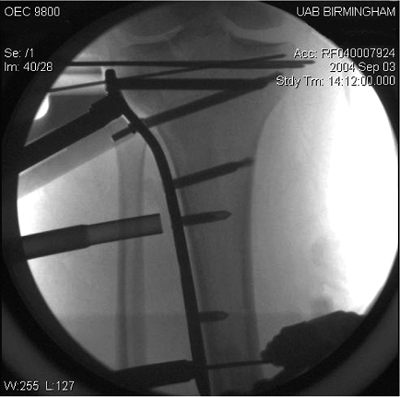

![]() |

Figure 27.12. Confirming location of the plate in the midlateral plane of the tibia via fluoroscopy.